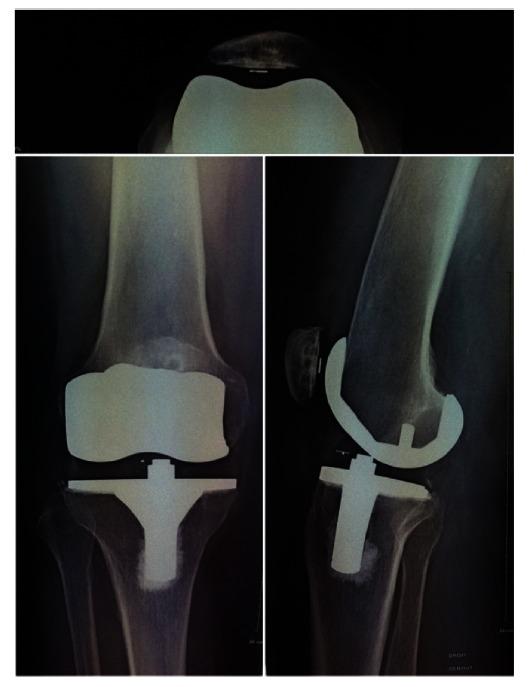

一款超一致旋转平台膝关节假体5.6年的功能与安全性:e.motion(®)UC-TKA超过5年的随访

Functionality and Safety of an Ultra-Congruent Rotating Platform Knee Prosthesis at 5.6 Years: More than 5- Year Follow-Up of the e.motion ((®)) UC-TKA.

Mobile bearing TKA prostheses were designed to minimize polyethylene wear by increasing implant conformity and reducing stresses between the articulating prosthesis components. It is the purpose of this study to assess the mid-term functionality and clinical outcome associated with a highly congruent mobile platform design, the e.motion(®) UC total knee prosthesis.

Functional and clinical outcomes were assessed after an average of 5.6 years (5.1 - 6.0 years) after total knee arthroplasty in 28 patients (24 women), aged 77.8±7.5 years. The Knee injury and Osteoarthritis Outcome Score (KOOS) was assessed. Secondary outcomes included the Knee Society Score (KSS), radiological evaluation of radiolucent lines and recording of adverse events.

The average KOOS subscore for the activities of daily life was 77.8 points after 5.6 years. Both the clinical and functional KSS improved at 2.4 and 5.6 years. Two patients showed radiolucent lines at 5.6 years. Adverse events over 5.6 years included 3 subluxations, 1 tilting and 1 misalignment of the patella. None of the prostheses were revised.

This pilot study shows promising outcomes for the e.motion(®) UC prosthesis. In the small sample, the implant performed comparably to the LCS prosthesis (the gold standard). There were no loosenings or revisions observed at 5.6 years.

活动平台全膝关节置换(TKA)假体旨在通过提高植入物的贴合度和减少关节假体部件之间的应力来使聚乙烯磨损最小化。本研究的目的是评估与高度贴合的活动平台设计e.motion(®)UC全膝关节假体相关的中期功能和临床结果。

对28例患者(24名女性)进行了研究,这些患者在全膝关节置换术后平均5.6年(5.1 - 6.0年),年龄为77.8±7.5岁。评估了膝关节损伤和骨关节炎疗效评分(KOOS)。次要结果包括膝关节协会评分(KSS)、透亮线的放射学评估以及不良事件的记录。

5.6年后,日常生活活动的平均KOOS子评分为77.8分。临床和功能KSS在2.4年和5.6年时均有所改善。两名患者在5.6年时出现透亮线。5.6年期间的不良事件包括3次半脱位、1次髌骨倾斜和1次髌骨排列不齐。没有假体进行翻修。

这项初步研究显示e.motion(®)UC假体有良好的结果。在小样本中,该植入物的表现与LCS假体(金标准)相当。在5.6年时未观察到松动或翻修情况。